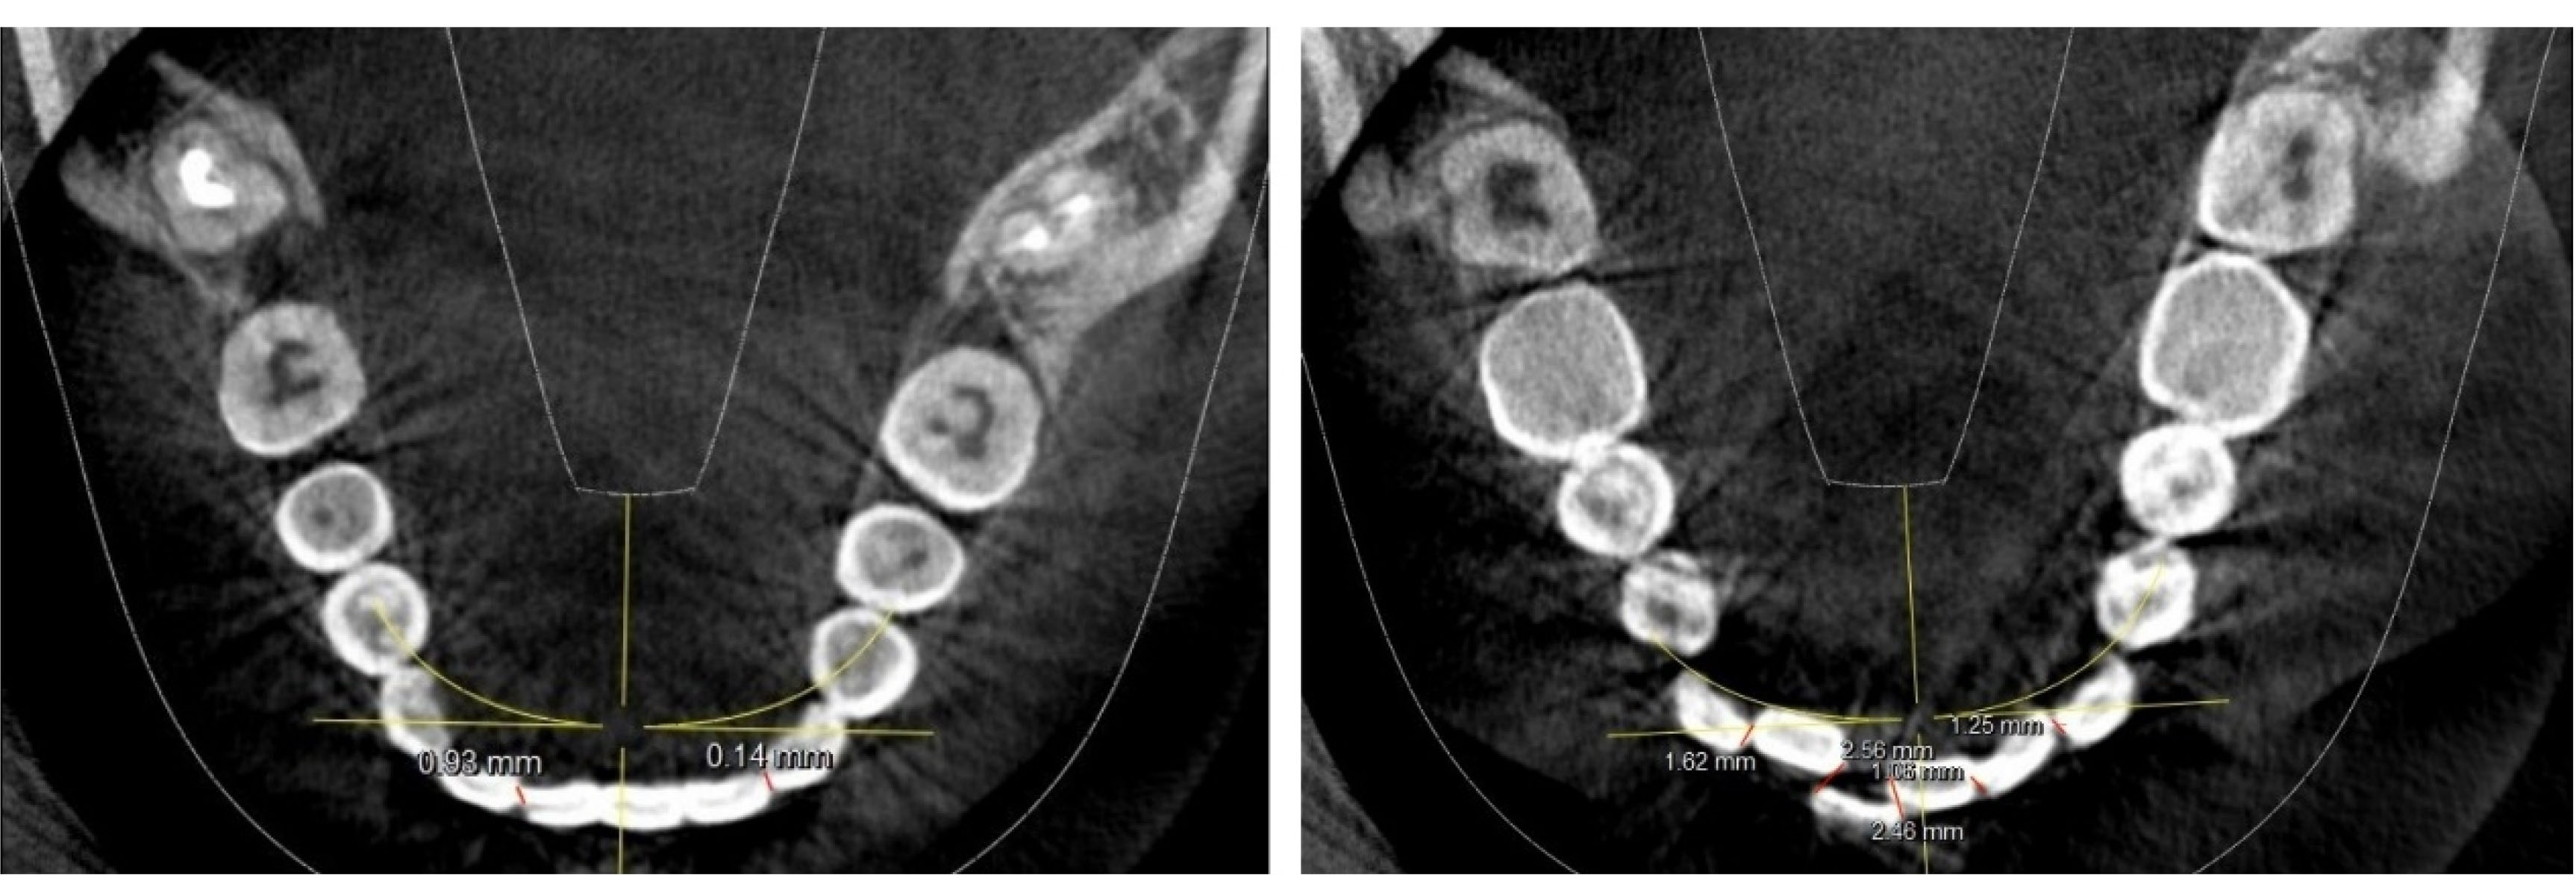

The images were viewed from the axial dimension to calculate mandibular incisor crowding. The images were adjusted in the axial view to the point where the incisal edges and the contact points of mandibular incisors were barely visible. The points were manually plotted from the mesial incisal edge of one tooth to the distal incisal edge of another tooth to make linear measurements. Such points were plotted from the mesial incisal edge of the left mandibular canine to the mesial incisal edge of the right mandibular canine, as shown in (). The linear measurements were summed up to obtain Little’s irregularity index score for that sample. The obtained values were tabulated and subjected to statistical analysis. SPSS 23 was used for statistical analysis. Descriptive statistics and Pearson’s correlation test were performed to determine the correlation between mandibular third molars and mandibular lower incisor crowding.

joddd-15-247-g001

Figure 1. Measurement of Little’s irregularity index using CBCT axial view.